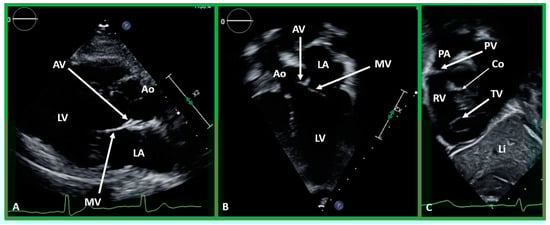

Ventricular Trabeculations and Shape

The morphologic LV is a smooth-walled structure with fine trabeculations and a foot-shaped appearance, whereas the morphologic RV has coarse trabeculations and a triangular shape. These features are demonstrated by echocardiographic (Figure 34) and angiographic (Figure 31, Figure 35 and Figure 36) studies. It should be noted that the characteristic trabecular pattern of the ventricles is seen irrespective of great vessel relationship: normally related great vessels (Figure 31 and Figure 34), transposed great arteries in levocardia (Figure 35) or transposed great arteries in dextrocardia (Figure 36).

Figure 34. Echo images demonstrating finely trabeculated left ventricle (LV) (A,B) and coarsely trabeculated right ventricle (RV) (A,C) in apical precordial views. The LV trabeculations are barely seen in (A) but are better seen in (B). Similarly, the RV trabeculations are better seen in (C). Aorta (Ao), left atrium (LA), and right atrium (RA) are labeled.

Atrioventricular Valve-to-Semilunar Valve Relationship

It has been established that AV valves go with the respective ventricular chambers in that the mitral valve is an essential part of the LV while the tricuspid valve is an integral part of the RV [10,11,13,28]. The morphologic LV has little or no conus musculature, and consequently, the mitral valve and aortic valve are in fibrous continuousness with each other (Figure 35A,B, Figure 36A and Figure 37A,B). However, in the morphologic RV, a muscular structure (crista supraventricularis) separates the tricuspid valve from the pulmonary valve, and therefore, fibrous continuity between the AV valve and semilunar valve (Figure 31A, Figure 35C,D, Figure 36B and Figure 37C) cannot be demonstrated. These features may be demonstrated in echocardiography (Figure 37) and angiography (Figure 31, Figure 35 and Figure 36).

Figure 37. (A,B). Echo images in the parasternal long axis (A) and modified apical four-chamber (B) views to demonstrate the atrioventricular valve-to-semilunar valve relationship. Note that the aortic (AV) and mitral (MV) valve leaflets are in fibrous continuity with each other, indicating that this ventricle is a morphologic left ventricle (LV). (C) Selected video frame in a subcostal view to demonstrate atrioventricular valve-to-semilunar valve relationship in a child with normally related great vessels demonstrating lack of continuity between the pulmonary (PV) and tricuspid (TV) valve leaflets due to conus (Co) separating them. Aorta (Ao), left atrium (LA), liver (Li), pulmonary artery (PA), and right ventricle (RV) are labeled.